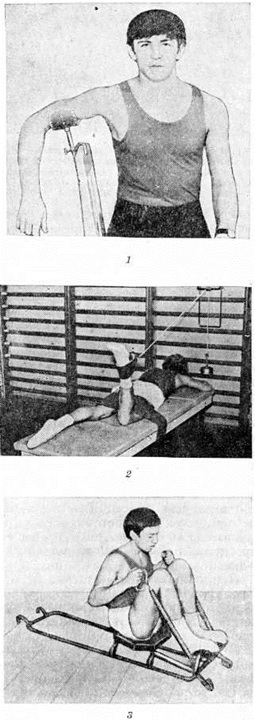

Всем больным с острым гематогенным Остеомиелит иммобилизируют поражённую конечность путём наложения гипсовой лонгеты, а на период проведения внутрикостных промываний — с помощью шины Белера. У детей до 2—3-летнего возраста для иммобилизации нижней конечности накладывают липкопластырное вытяжение по Шеде, верхней конечности — повязку Дезо. Иммобилизацию осуществляют до полного стихания воспалительных явлений и восстановления функции конечности.

Подготовка больных к операции должна включать лечебный мероприятия, направленные на уменьшение воспалительных явлений в зоне поражения (промывание свищей антисептическими растворами и растворами протеолитических ферментов, физиотерапия и другие), санацию кожи операционного поля, активацию иммунных реакций и дезинтоксикацию организма, на улучшение функций жизненно важных органов и систем.

Радикальные операции обычно выполняют под наркозом. Операция состоит в иссечении всех свищей (реже — выскабливании коротких свищей), трепанации кости с раскрытием остеомиелитической полости на всем протяжении, секвестрэктомии, удалении из полости инфицированных грануляций и гноя, иссечении внутренних стенок полости до непоражённой костной ткани, многократном промывании полости растворами антисептиков (фурацилина, фурагина, риванола, формалина, антибиотиков и другие), пластике полости и зашивании раны наглухо.

© Ordo Deus, 2010. При копировании ссылка на сайт http://www.ordo-deus.ru обязательна. |